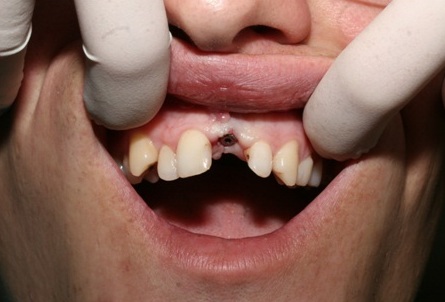

The surgery of an implant opening without a vestibule-oral graft throwing away was carried out in six months after the surgical stage. Availability of a sufficient amount of soft tissues in the region of implant placement made it possible to give up the usage of zirconium abutments and make use of a standard anatomic abutment to obtain positive clinical result.

The permanent metal-ceramic crown was manufactured later on.

Complete restoration of aesthetic look and function (Photo 9 and 10).